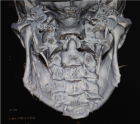

Sagittal split osteotomy (SSO) of the mandible is still an important part of orthognathic surgery, but “bad split” fractures that happen during the surgery are still a big problem. This report describes a rare case of bilateral bad split associated with highly compact mandibular bone (D1–D2 type) in a 53-year-old male undergoing mandibular advancement. The bone was too hard for the piezoelectric and rotary tools to work, and there was very little bleeding. This caused fractures in the cortex and lingual. Postoperative computed tomography confirmed the presence of highly dense bone, correlated with delayed healing and recurrence. Consistent pre-surgical CT scanning for an assessment of the density of the mandibular bone can provide essential information about the potential risk of the osteotomy procedure in the patient. Performing a careful bone quality and density examination pre-operatively will allow the surgeons to select the most appropriate instruments and surgical techniques that will fit the patient’s individual anatomy. Such a point escalates to being very significant when dealing with the geriatric population, as bone density increase can not only alter the fracture behavior but also the recovery process during and after surgery. The inclusion of regular CT-based bone density evaluations into the preoperative routine not only facilitates the anticipation of surgical difficulties but also results in safer and more efficient osteotomies.

Figure 4